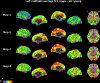

Results: The disease epicenter was identified in the left midbrain tegmental region. Compared with age-matched control subjects, patients with PSP-RS showed progressively widespread decreased SFC of the midbrain with striatal and cerebellar regions through direct connections and sensorimotor cortical regions through indirect connections. A correlation was found between average link-step distance from the left midbrain in healthy subjects and brain volumes in patients with PSP-RS (r = 0.38, P < 0.001).

Conclusions: This study provides comprehensive insights into the topology of functional network rearrangements in PSP-RS and demonstrates that the brain architectural topology, as described by SFC propagating from the disease epicenter, shapes the pattern of atrophic changes in PSP-RS. Our findings support the view of a network-based pathology propagation in this primary tauopathy. © 2024 The Author(s). Movement Disorders published by Wiley Periodicals LLC on behalf of International Parkinson and Movement Disorder Society.